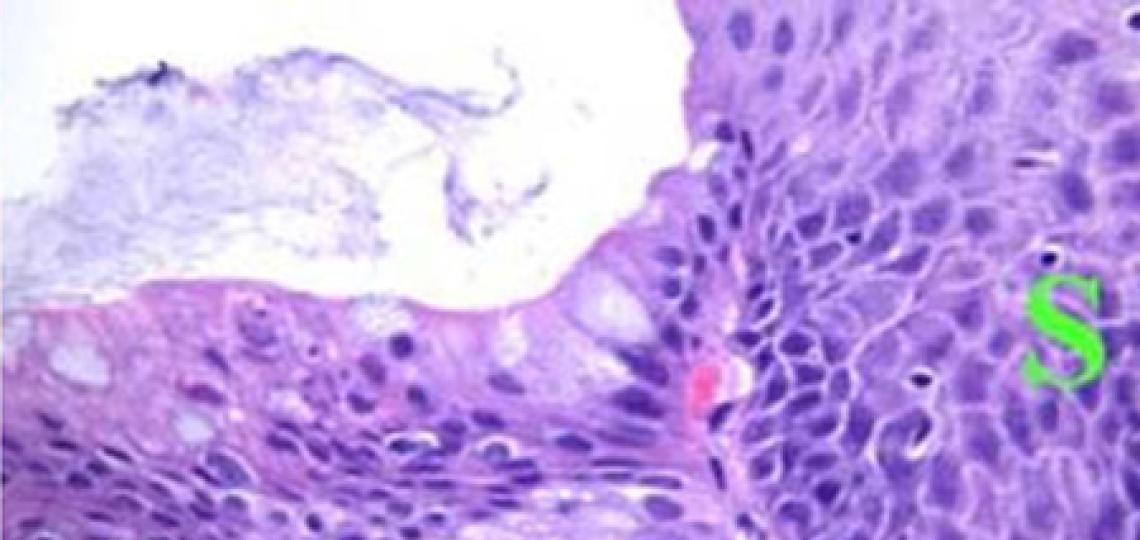

“Although the main experiments were conducted in stomach chief cells, we observed that injury to other tissues, such as pancreatic acinar cells (which regenerate after pancreatitis) and human gastric tissues showing early cancer related changes, also triggered destruction of STK38 by self-digestion and consequent YAP1 activation,” Mills said. “This suggests that the STK38–YAP1 switch may be a general mechanism for mature cells to regain regenerative properties – not just in the stomach, but across many organs. Having a better understanding of paligenosis can lead to improved strategies for tissue regeneration and potentially cancer.”